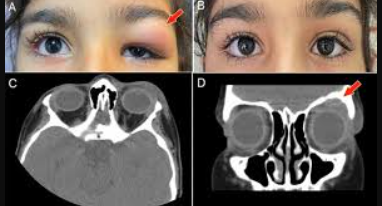

Visual acuity and visual field tests are a good screen to test for chiasmal involvement. Neuroimaging may also be needed (i.e. MRI (magnetic resonance imaging)). In some cases, endocrinologic evaluation should be considered when the cause is pituitary adenoma, which is the most common extrinsic cause of chiasmal syndrome. A pattern electroretinogram may be measured to predict the visual prognosis of patients with chiasmal compression.